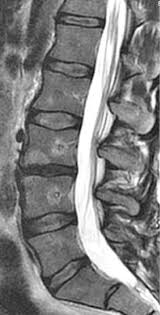

Ο σπονδυλογενής πόνος αναπτύσσεται όταν οι σπονδυλικές τελικές επιφυσιακές πλάκες υποστούν βλάβη ή φλεγμονή. Αυτό μπορεί να οδηγήσει σε χρόνιο πόνο που είναι ανθεκτικός στις συντηρητικές θεραπείες.

Η θεραπεία στοχεύει τα sinuvertebral nerves του σπονδυλικού σώματος, τα οποία μεταδίδουν σήματα πόνου από τις τελικές αποφυσιακές πλάκες. Με την απενεργοποίηση των νεύρων αυτών, διακόπτεται η ροή επώδυνων ερεθισμάτων πόνου από τον σπόνδυλο προς το κεντρικό νευρικό σύστημα. Σταδιακά ο πόνος υποχωρεί, με το τελικό αποτέλεσμα να εγκαθίσταται συνήθως μέσα σε 3 μήνες. Ο ασθενής μπορεί να επιστρέψει στην καθημερινότητά του μέσα σε μια εβδομάδα από την παρέμβαση.

Κατά τη διάρκεια της επέμβασης , ένας ειδικός καθετήρας με ενσωματωμένο ηλεκτρόδιο εισάγεται διαδερμικά στον σπόνδυλο μέσω των αυχένων του σπονδυλικού σώματος εκατέρωθεν. Με τη χρήση της ενέργειας των ραδιοσυχνοτήτων, τα ενδοσπονδυλικά νεύρα θερμαίνονται και μαραζώνουν, παύοντας να μεταφέρουν επώδυνα ερεθίσματα.